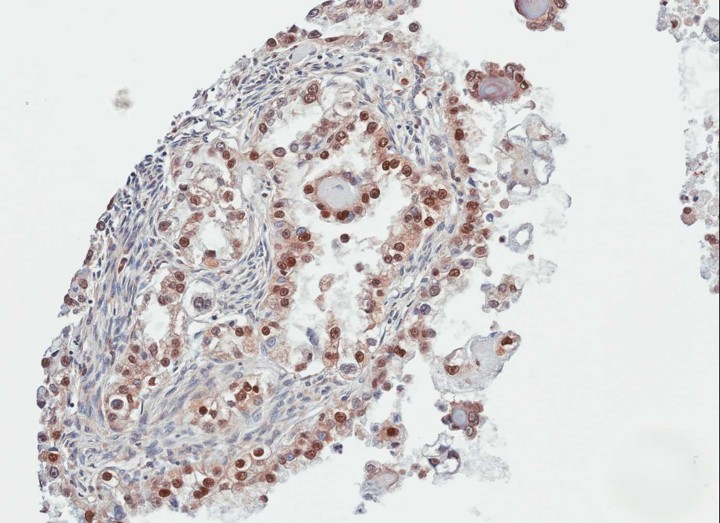

- Immunohistochemical analysis of paraffin-embedded OVCA, using PARP3 antibody at 1: 100 dilution.